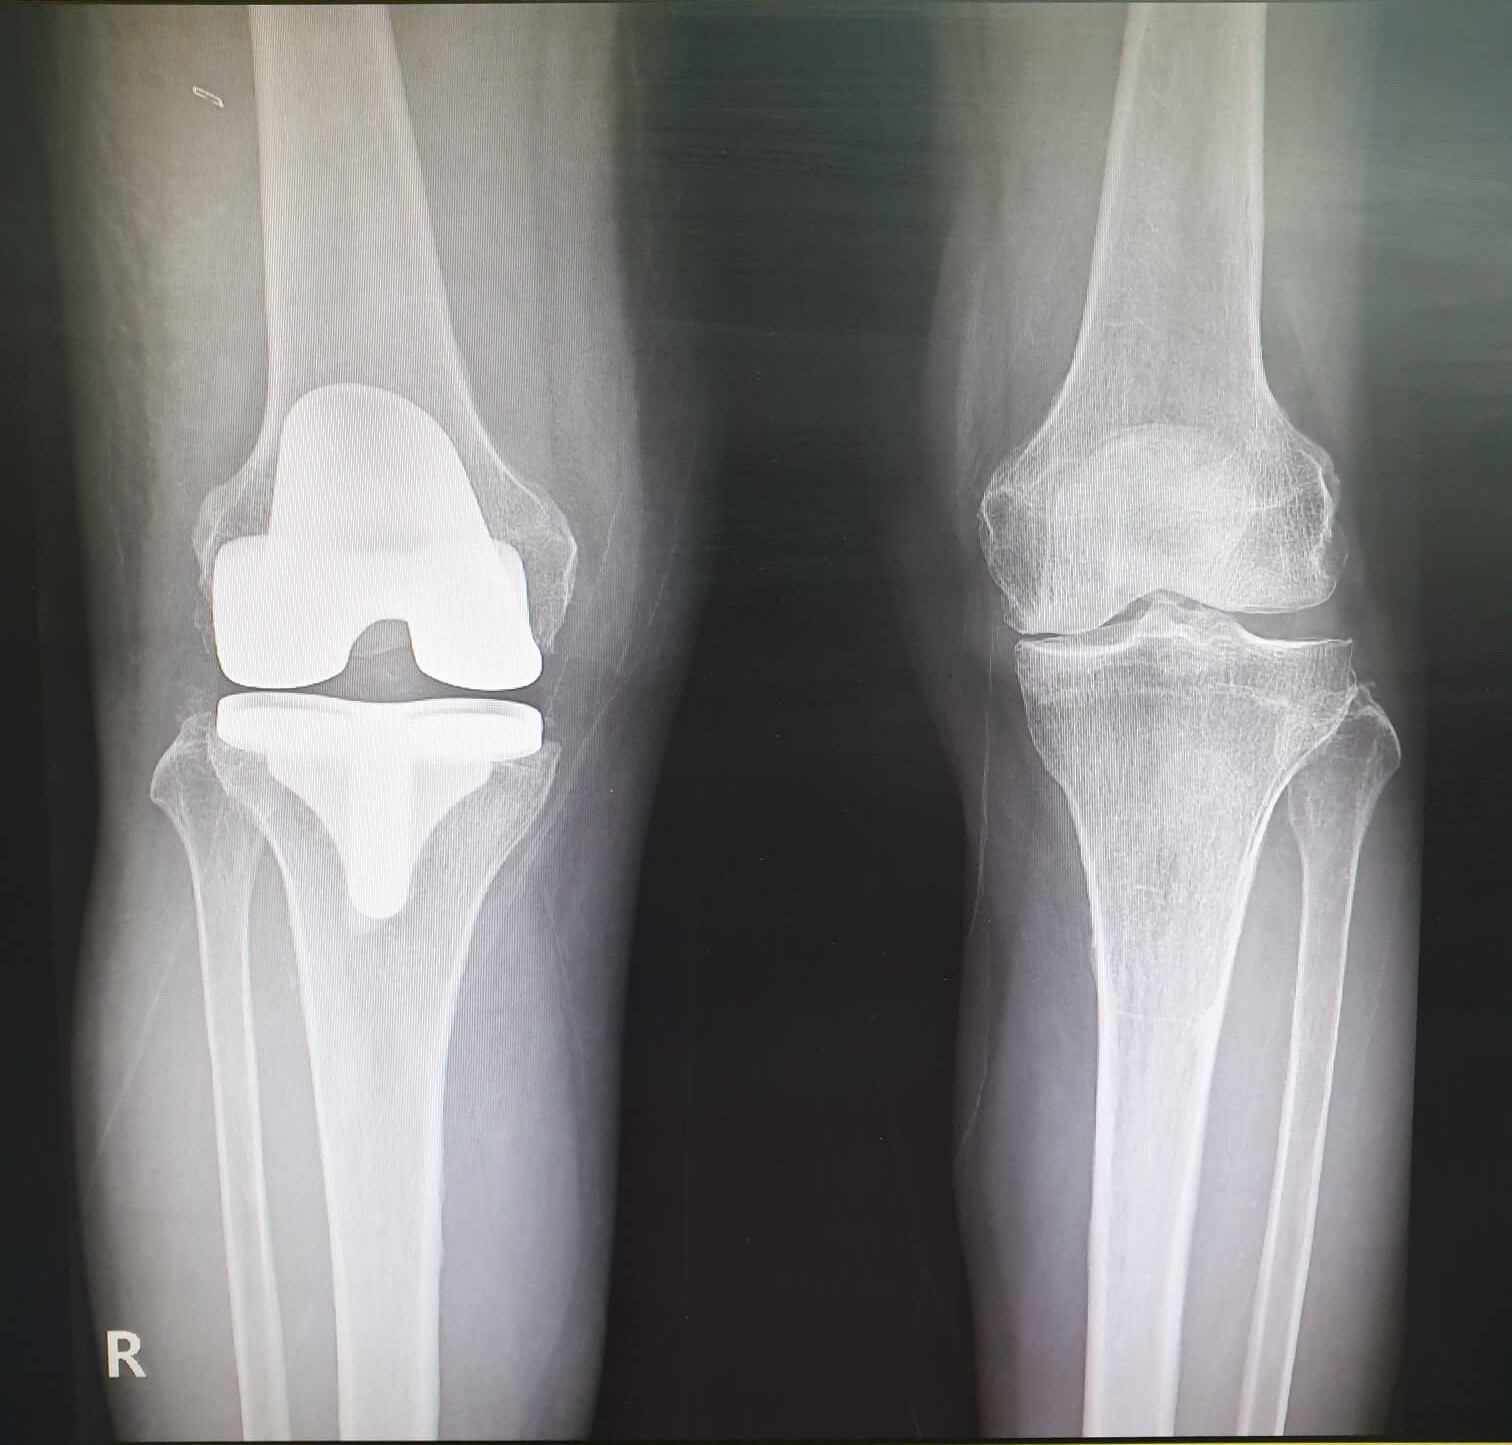

무릎의 퇴행성 관절염이나 류마티스 관절염으로 인해 관절이 파괴 된 경우 관절 연골과 뼈를 제거하고 관절 표면을 금속 삽입물과 고밀도 플라스틱으로 교체 삽입하는 수술을 말합니다.

수술을 받은 환자의 대부분의 경우(90%이상) 눈에 띄게 통증이 감소하고 일상 생활에서 자유로움을 느낍니다. 산책이나 수영, 골프, 운전, 가벼운 등산, 각종 취미 활동을 큰 통증없이 즐길 수 있게 됩니다.